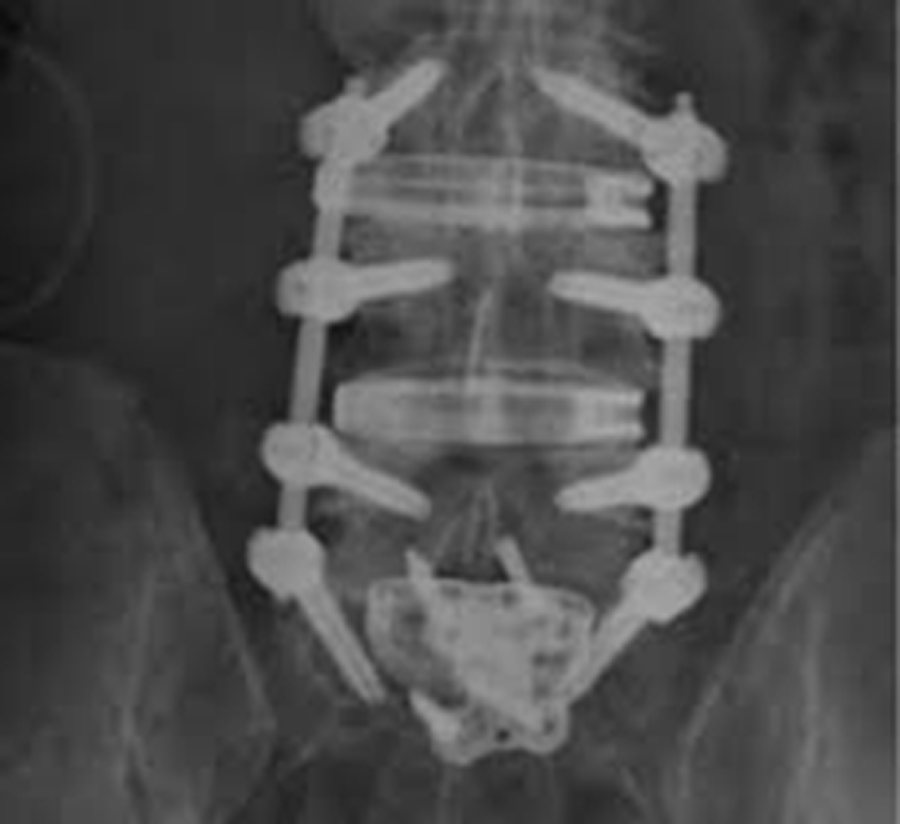

The patient underwent L3-S1 anterior reconstruction with indirect decompression (utilizing the UNLEASH™ ATP Procedural Solution L3-5 and ALIF L5-S1) and Percutaneous Posterior Segmental Pedicle Screw Fixation (Fig 5). Systems used were the following:

- INSIGHT® Lateral Access System (L3-L5)

- CONDUIT™ Lateral Interbody (L3-L5)

- CONDUIT™ ALIF Interbody and Aegis plate (L5-S1 with SYNFRAME® Access and Retractor System)

- VIPER PRIME® Screws: Posterior Pedicle Screw Instrumentation L3-S1